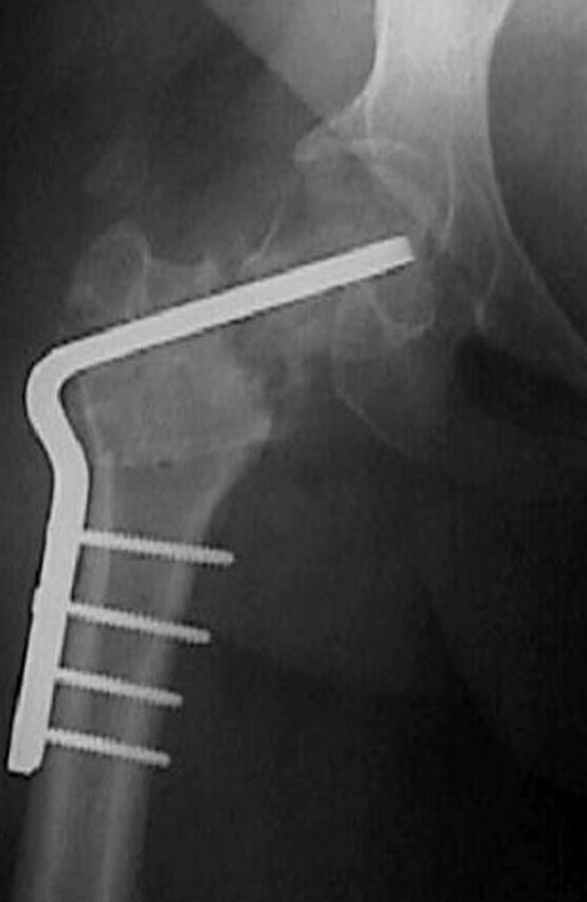

5:24 Рентгенограмма таза, вызывают врача ортопеда (снимок N1), его диагноз: закрытый переломо-вывих правого тазабедренного сустава, получает добро на закрытую репозицию в приемном отделении

7:30 начало операции, больной на спине, попытка репозиции после анестезии N3, укладка больного на боку, доступ Kocher- Langenbeck, состояние седалищнего нерва около 2.5см кровоподтек, через joistick головка бедра приподнята, освобовождение сустава, фрагмент заднего края более 3х4 см репонирован на свое место. После промывания

сустава, репозиция вывиха (N4), фиксация фрагмента 2.7(4) мм шурупами и допольнительно реконструктивной пластиной на 8 дырок, фиксация 3.5мм шурупами проксимально и дистально.

Интраоперционные N5 косая запирательная и N6 подвздошный снимок

11:50 больной в послеоперационной, рентгенограмма N7, компьютерная томограмма в тот же день N8-10

На рисунке N1 предоперационный план лечения ложного сустава шейки бедра- линия ложного сустава, угол и направление введения импланта, клиновидная остеотомия в градусах и миллиметрах, второй снимок после коррекции, расчет, на сколько удлиняется конечность и размеры импланта;

N3 рисунок окончательный снимок, после операции моя рентгенограмма должен выглядеть примерно как эта картина. На N4 снимке клин перед удалением; N5 послеоперации 3 нед.; N6 окончательная рентгенограмма.

варус при проксимальном отделе 95 градусной пластиной.